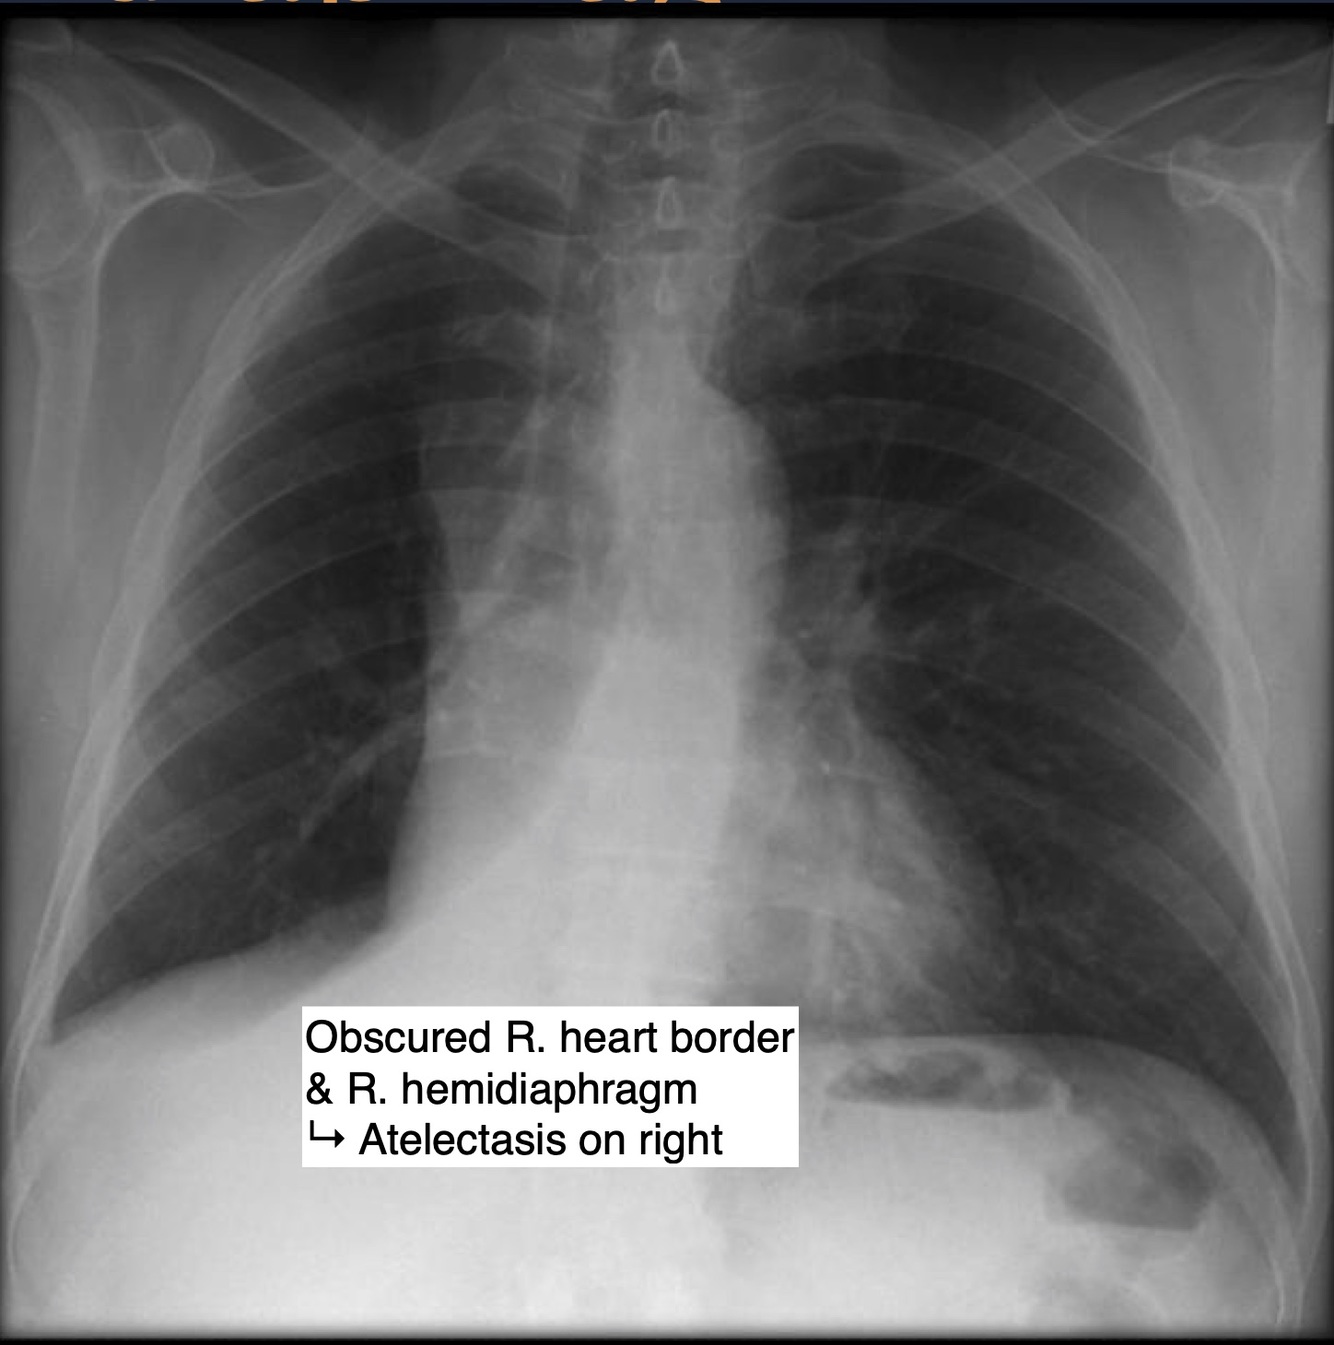

Atelectasis

Definition

Collapse of alveoli.

Causes

Lobar Atelectasis

Radiological sign ⇒ volume loss